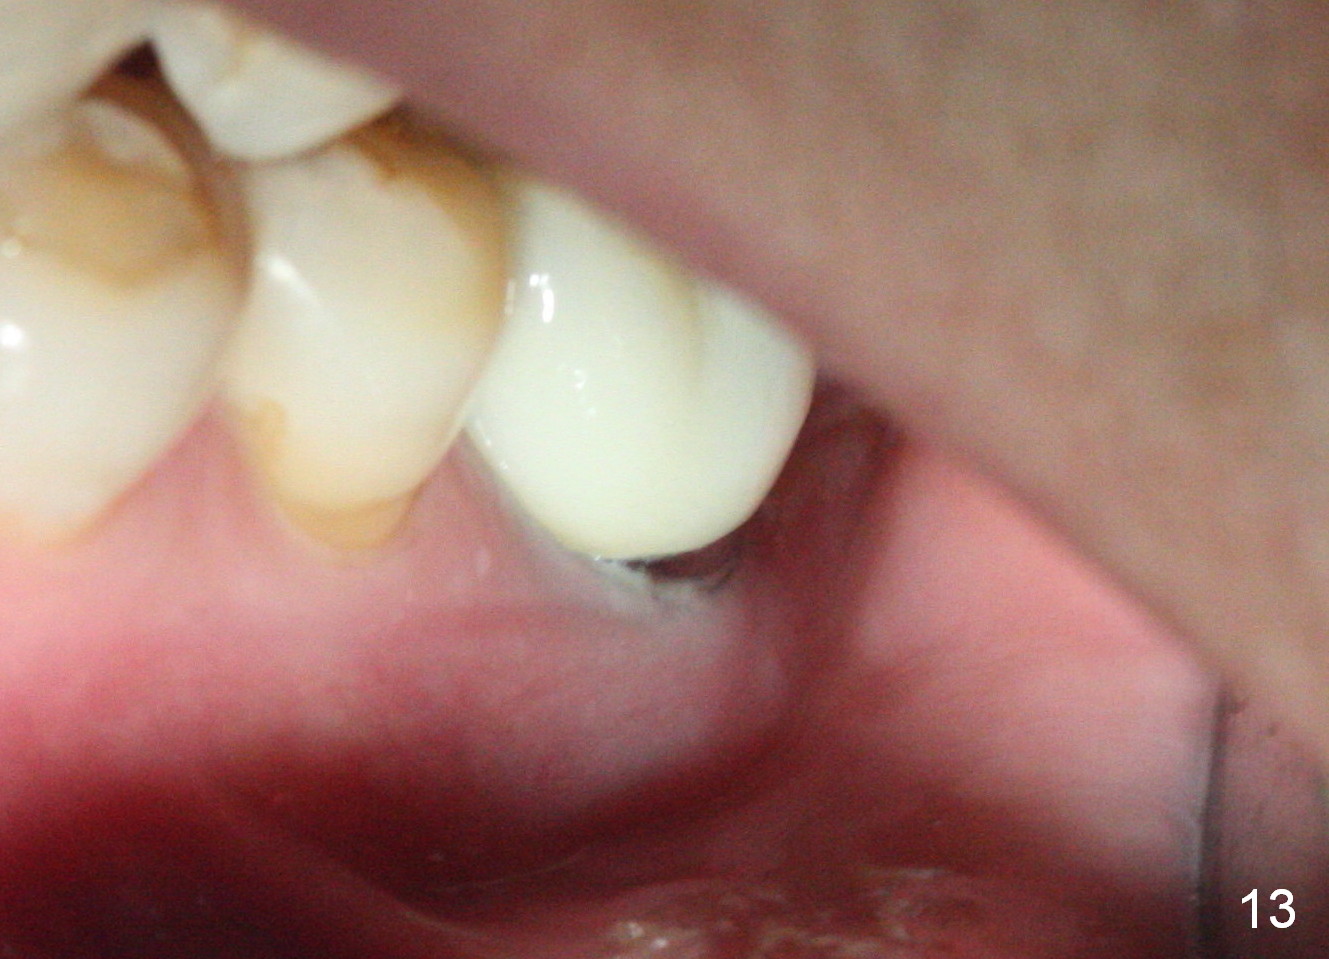

The patient returns for #19 restoration one year postop. The distal coronal threads appear not covered by bone (Fig.10 *) with distobuccal gingival recession (Fig.11). The buccal bulging (Fig.11 arrowheads) may be related to thin or no buccal plate. Bone graft at time of immediate implant may decrease the likelihood. In addition, the implant is placed buccally slightly (Fig.12). The gingival recession appears to have decreased 1 year 9 months post cementation (Fig.13). A thick keratinized gingiva forms around the implant at #8 1 year 11 months post cementation. There seems to be no bone loss 2.5 years post cementation (Fig.14,15, as compared to Fig.10)